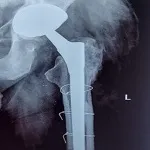

Quality and affordable healthcare has long been the essence in the field of medical sciences & treatment. Every patient expects an early diagnosis and a planned approach to treatment procedures with affordability and access to quality healthcare. Knee replacement, Hip replacement, Fracture treatment are being done by Dr.P.Sankaralingam at very affordable costs without compromising on quality.

Dr.P.Sankaralingam M.S(ortho)., DNB (ortho).,MNAMS is an experienced senior consultant Orthopaedic surgeon who does about 350 joint replacement surgeries per year in addition to treatment of Trauma cases.

Standard Hospital, Chennai’s Centre of Excellence for Orthopaedics offers minimally invasive surgeries for faster recovery.